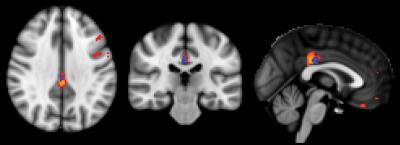

This image illustrates the direct comparison between the different groups. The biggest difference is present between stable controls and MCI, indicated in red-yellow, notably in the posterior cingulate cortex. The comparison of stable versus deteriorating controls (blue) shows differences in the same region yet less pronounced. The comparison between deteriorating controls and MCI revealed no significant differences.